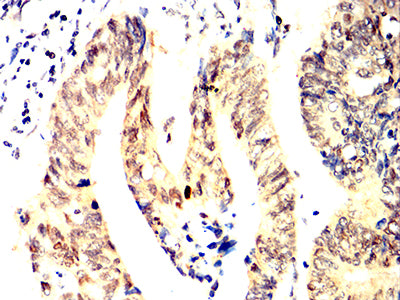

- Immunohistochemical analysis of paraffin-embedded human prostate cancer tissues using ACHE mouse mAb with DAB staining.

- Immunohistochemical analysis of paraffin-embedded human rectum cancer tissues using ACHE mouse mAb with DAB staining.